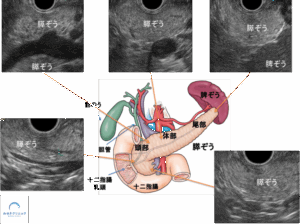

特に超音波内視鏡(EUS)は、胃や十二指腸から膵臓を近くで観察できるため、腹部エコーやCTでは見えにくい小さな変化も詳しく評価することが可能です。

特に超音波内視鏡(EUS)は、胃や十二指腸から膵臓を近くで観察できるため、小さな変化や壁在結節などを詳しく評価するのに有用な検査です。

胃や十二指腸から膵臓を近くで観察できる精度の高い検査です。

MRIやCTでは見えにくい変化を詳細に評価できます。

超音波内視鏡(EUS)は、胃や十二指腸の中から膵臓を観察する検査です。

膵臓に非常に近い位置から観察できるため、

数ミリ程度の小さな変化まで確認できるのが大きな特徴です。

超音波内視鏡(EUS)では、胃や十二指腸から膵臓を近くで観察することができます

超音波内視鏡(EUS)は、内視鏡の先端に超音波装置を付けた検査で、胃や十二指腸の中から膵臓を近くで観察することができます。

腹部エコーやCTでは見えにくいごく小さな膵がんや膵嚢胞の内部構造を詳しく評価できるため、膵臓の精密検査として非常に重要な役割を担います。